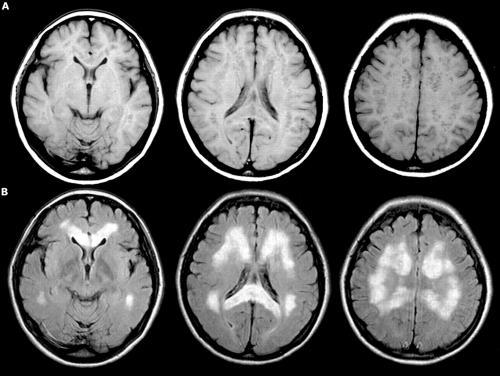

Теперь же были обнаружены следы нескольких типов грибков. Это объясняет разницу в симптоматике у людей и, собственно, саму симптоматику - агрессивную реакцию иммунитета. Правда, не исключено, что грибковая инфекция - результат ослабленного иммунитета при болезни Альцгеймера.